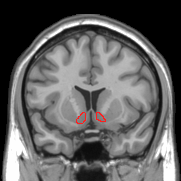

とくに側坐核(そくざかく)は「快感の中心地」とも呼ばれ、甘味摂取時にはドーパミンがこの領域で増加します。

側坐核の位置(赤い丸)

ところが、高スクロース摂取を継続したラットでは、側坐核におけるドーパミン濃度やチロシン水酸化酵素(TH)の発現が低下することがわかりました。

これは、快感の刺激が長期的には報酬感覚の減退や過食につながる「負のフィードバック」回路を形成している可能性を示します。

さらに、側坐核の外側(シェル)と内側(コア)という2つの領域におけるドーパミンの挙動の違いについても分析が進んでおり、シェル領域の方が長く強い反応を示すことが明らかとなっています。

これは薬物依存に近い形で、砂糖が「習慣化しやすい報酬刺激」であることを裏づけています。